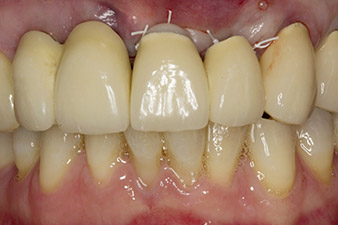

When the patient first presented, teeth 21, 22 and 23 had been restored with splinted crowns, now 19 years old, which were bonded to the implants at positions 12/11 by an attachment (cf. Fig. 2).

Tooth 23 displayed a horizontal-coronal fracture and was restored with a post and core build-up for the temporary restoration. The plan was to place a zirconium oxide bridge on the existing implants at positions 12 and 11 and to place two new implants at positions 22 and 23.

In this case study, the situation was resolved with an implant at position 22 in the first procedure and an additional one at the position of the extracted tooth 23 later in the course of the treatment. The second implant was inserted following successful osseointegration of implant 22. The revised bridge was reinserted until implant 23 healed in place and the shaping for the permanent restoration was complete. The advantages of this gradual approach include the implants’ being able to accept loads more resiliently and mature hard and soft tissues (5).